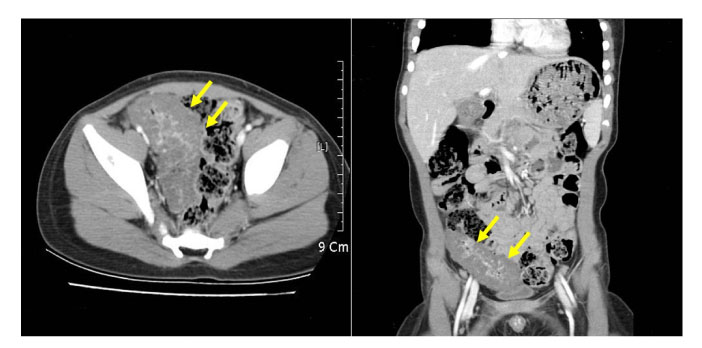

Fig. 1

Abdominopelvic CT scan with contrast medium, showing circumferential thickening of the small bowel with central enhancement in the pelvic cavity.

Fig. 1 Abdominopelvic CT scan with contrast medium, showing circumferential thickening of the small bowel with central enhancement in the pelvic cavity.